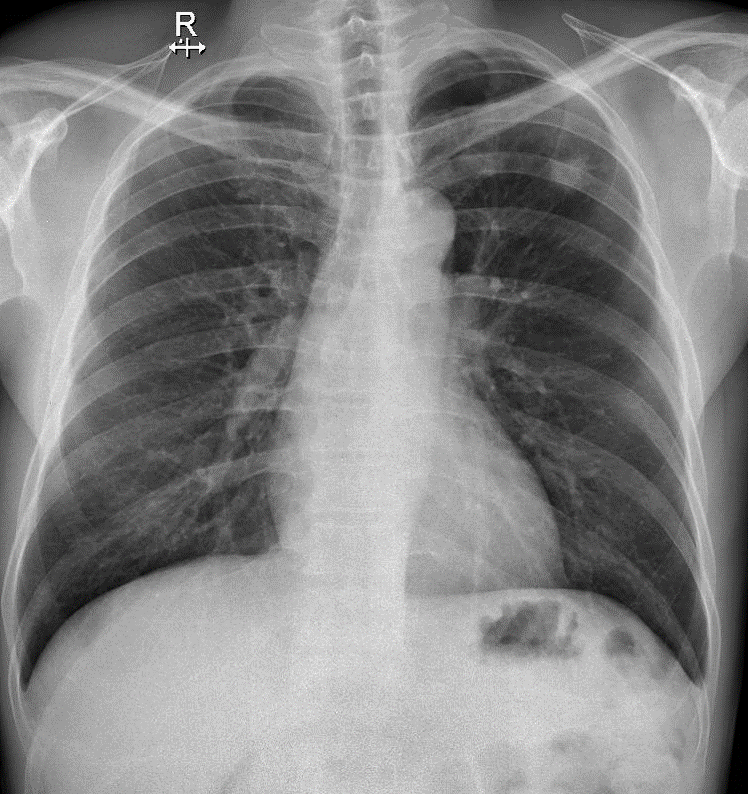

Hãy phân tích tình huống NAM 53 tuổi -CĐ: U ác phế quản phổi

1-U thùy trên phổi (T): tuberculoma, harmatoma, ...